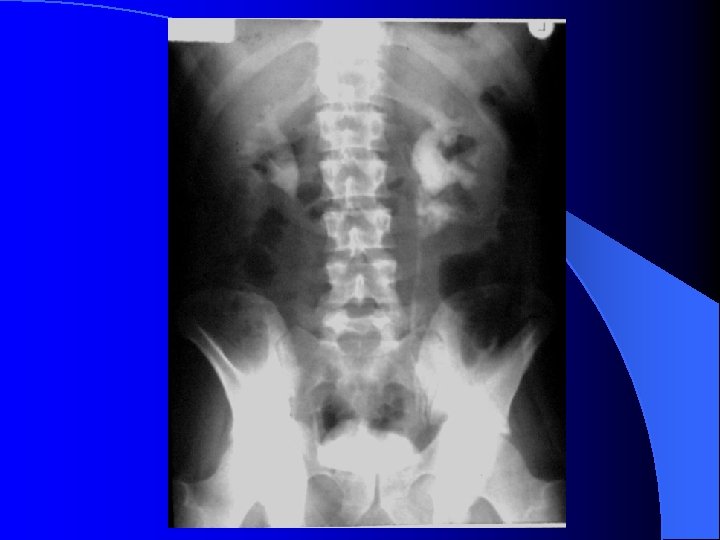

RRVS tehnic - ultimele doua coaste ( sup. ) - simfiza pubiana (inf. ) l calcificări - aparat urinar ( parenchim renal, calculi, prostatice ) - extraurinare ( arteriale, vezica biliara, pancreatice, ganglionare, fleboliti. . ) l umbre renale - pozitie, dimensiuni, contururi, intensitate l umbra m. psoas l

RRVS Nefrograma normală